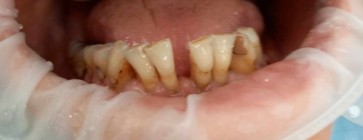

Błędy diagnostyczne oraz techniczne w leczeniu…

Damian Dudek, Maciej Jagielak, Aldona Chloupek, Oliwia Warmusz, Edyta Reichman-Warmusz